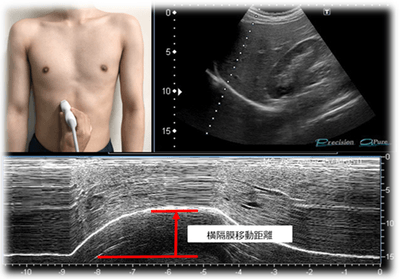

慢性閉塞性肺疾患患者に対する吸気筋トレーニングの効果を検証 横隔膜移動距離が吸気筋トレーニングの評価項目として有用と証明